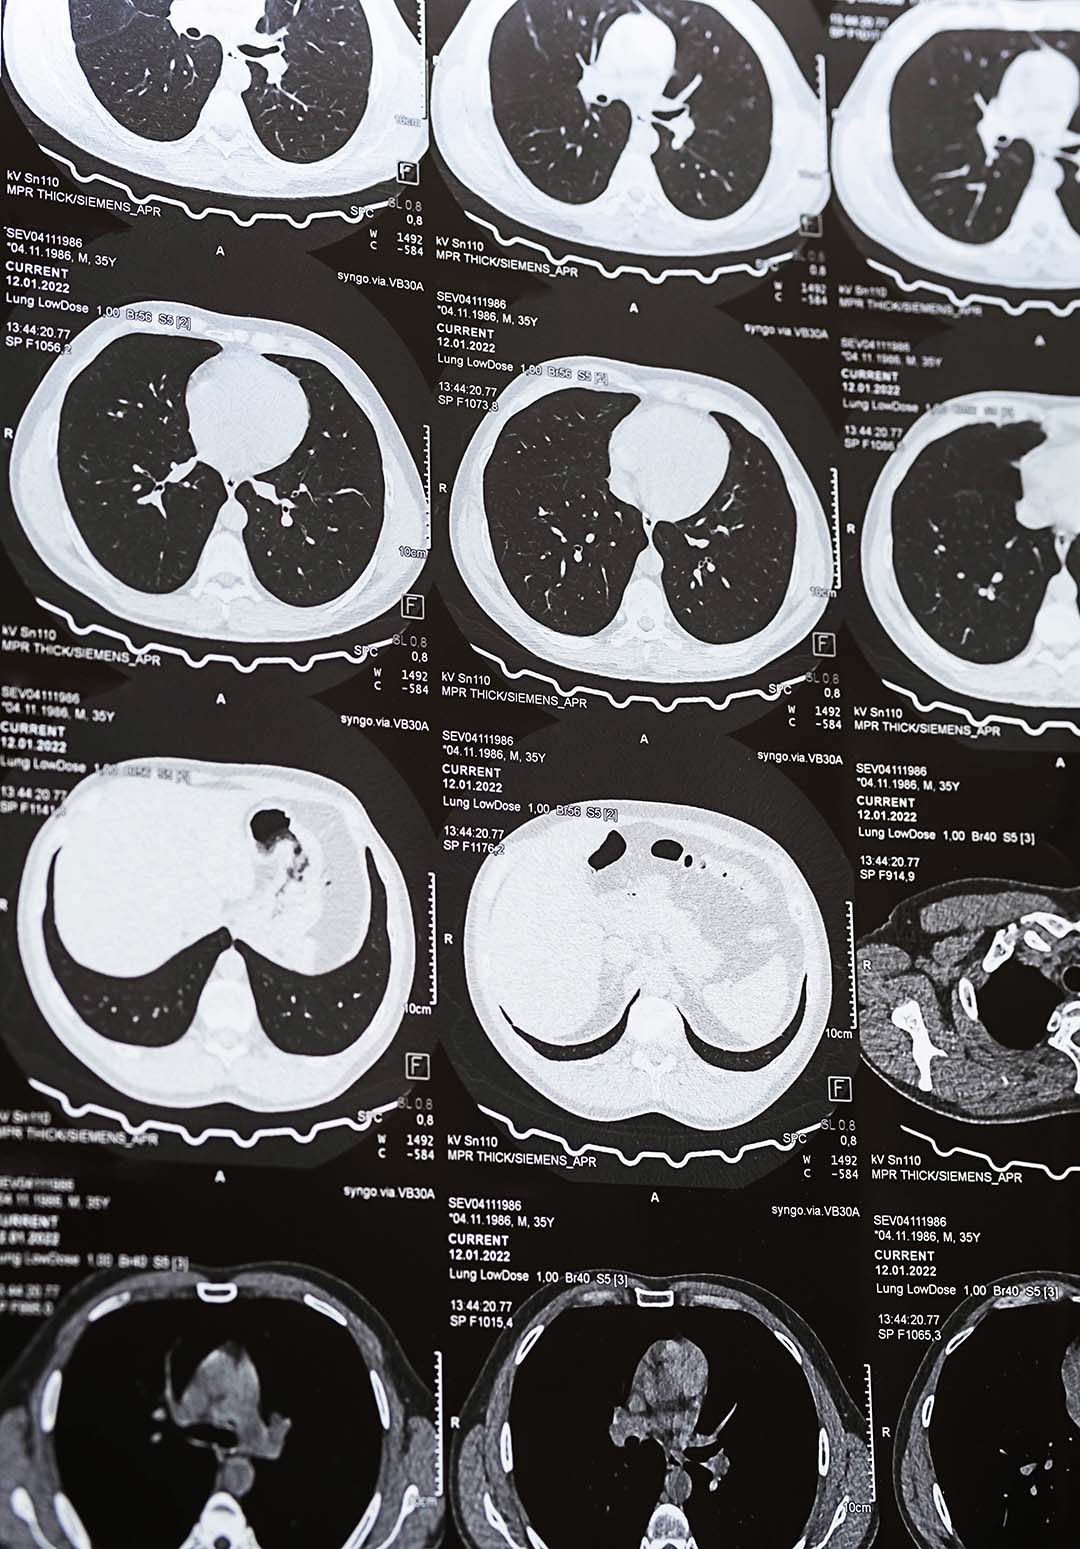

- CT pulmonary angiography (CTPA) – This is the most common test used today. It uses contrast dye to create detailed pictures of the pulmonary arteries so doctors can see blood clots blocking blood flow.